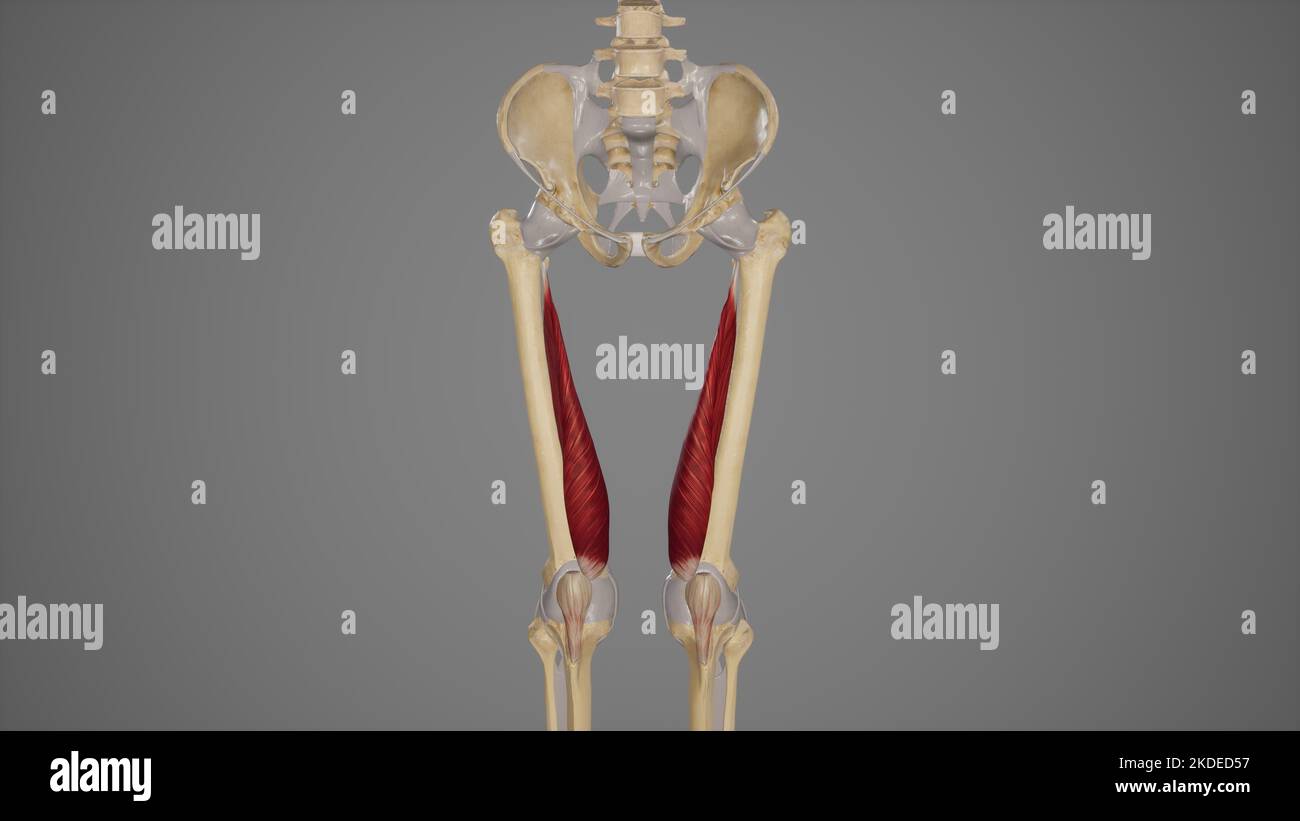

Illustration médicale du muscle vastus lateralis Banque D'Imageshttps://www.alamyimages.fr/image-license-details/?v=1https://www.alamyimages.fr/illustration-medicale-du-muscle-vastus-lateralis-image490198498.html

Illustration médicale du muscle vastus lateralis Banque D'Imageshttps://www.alamyimages.fr/image-license-details/?v=1https://www.alamyimages.fr/illustration-medicale-du-muscle-vastus-lateralis-image490198498.htmlRF2KDED56–Illustration médicale du muscle vastus lateralis